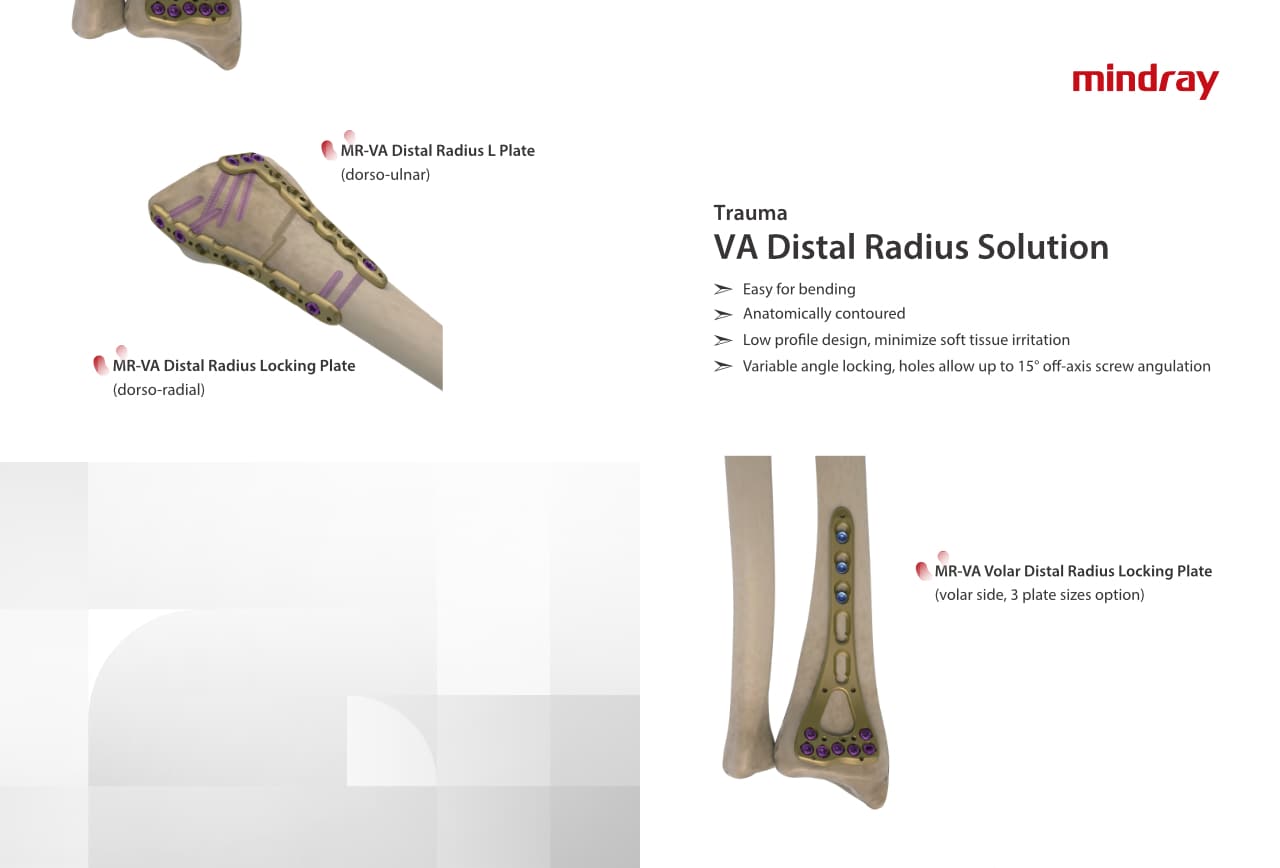

–Ю—А—В–Њ–њ–µ–і–Є—З–µ—Б–Ї–Њ–µ –њ–Њ–і—А–∞–Ј–і–µ–ї–µ–љ–Є–µ –Ї–Њ–Љ–њ–∞–љ–Є–Є Mindray, —А–∞—Б–њ–Њ–ї–Њ–ґ–µ–љ–љ–Њ–µ –≤ –£—Е–∞–љ–µ, —П–≤–ї—П–µ—В—Б—П –Њ–і–љ–Є–Љ –Є–Ј –≤–µ–і—Г—Й–Є—Е –њ—А–Њ–Є–Ј–≤–Њ–і–Є—В–µ–ї–µ–є –Њ—А—В–Њ–њ–µ–і–Є—З–µ—Б–Ї–Њ–є –њ—А–Њ–і—Г–Ї—Ж–Є–Є –Є–Ј –Ъ–Є—В–∞—П. –Ю–љ–Њ –Ј–∞–љ–Є–Љ–∞–µ—В—Б—П –Є—Б—Б–ї–µ–і–Њ–≤–∞–љ–Є—П–Љ–Є –Є —А–∞–Ј—А–∞–±–Њ—В–Ї–Њ–є, –њ—А–Њ–Є–Ј–≤–Њ–і—Б—В–≤–Њ–Љ –Є –Љ–∞—А–Ї–µ—В–Є–љ–≥–Њ–Љ —В—А–∞–≤–Љ–∞—В–Њ–ї–Њ–≥–Є—З–µ—Б–Ї–Є—Е –Є —Б–њ–Є–љ–∞–ї—М–љ—Л—Е –Є–Ј–і–µ–ї–Є–є, –њ—А–Њ–і—Г–Ї—Ж–Є–Є –і–ї—П –∞—А—В—А–Њ–њ–ї–∞—Б—В–Є–Ї–Є –Є –і—А—Г–≥–Є—Е —Е–Є—А—Г—А–≥–Є—З–µ—Б–Ї–Є—Е –Є–Ј–і–µ–ї–Є–є. –° –Љ–Њ–Љ–µ–љ—В–∞ —Б–≤–Њ–µ–≥–Њ –Њ—Б–љ–Њ–≤–∞–љ–Є—П –≤ 1999 –≥–Њ–і—Г –Љ—Л —Г—Б–њ–µ—И–љ–Њ –њ—А–Њ—И–ї–Є —Б–µ—А—В–Є—Д–Є–Ї–∞—Ж–Є—О ISO 9001, ISO 13485 –Є CE, –≤—Л–і–∞–љ–љ—Г—О T?V –Є —Н–Ї—Б–њ–Њ—А—В–Є—А—Г–µ–Љ –њ—А–Њ–і—Г–Ї—Ж–Є—О –≤ –±–Њ–ї–µ–µ —З–µ–Љ 50 —Б—В—А–∞–љ –њ–Њ –≤—Б–µ–Љ—Г –Љ–Є—А—Г.